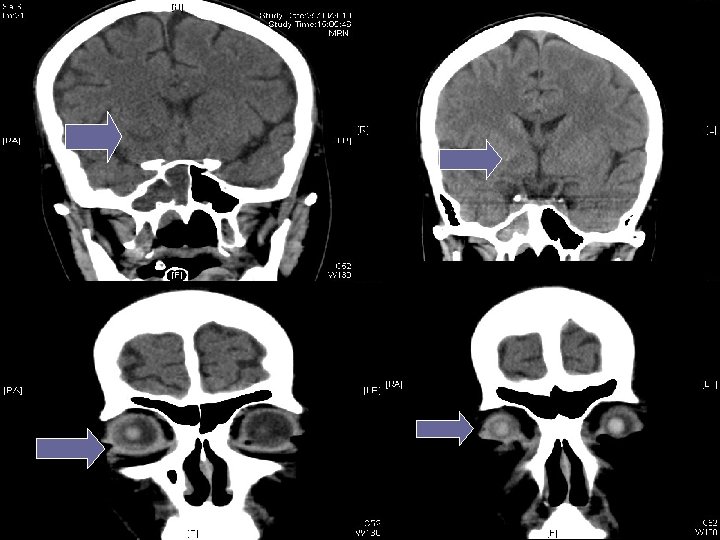

Contrast CT brain on 27 th Aug

(4) Neurologist assessment: summary Initial presenting illness n Bulbar palsy with normal NCT, but clinically nil response to IVIG and steroid Deterioration right now n Cerebral dysfunction with raised CSF protein n Hypointensities in bilateral temporal and Rt BG Need to consider other diagnosis n Sinusitis with orbital + CNS extension n For contrast MRI brain + skull base

Searching for an answer, again…. . n n n n n 9 th July: Plain CT Brain (Hospital A) 7 th Aug: Plain CT Brain (Hospital A) 25 th August: Plain CT Orbit (Hospital A) 27 th August: Contrast CT brain + Sinus 4 th September: MRI brain + brainstem 4 th September: Plain CT brain 10 th September: Contrast CT brain 11 th September: Plain CT sinus 15 th September: MRI brain + DWI

Summary of progression • June/ 2010 n • July/ 2010 n • Early Aug/ 2010 n • Late Aug/ 2010 n • Sept/ 2010 n Lt face weak Bulbar palsy Dilated Rt pupil and uveitis Endophthalmitis and high fever Deep coma, tetraplegia, high fever n n n Nil imaging Facial neuritis Bilateral basal ganglia change Bilateral temporal + BG + thalami + pons